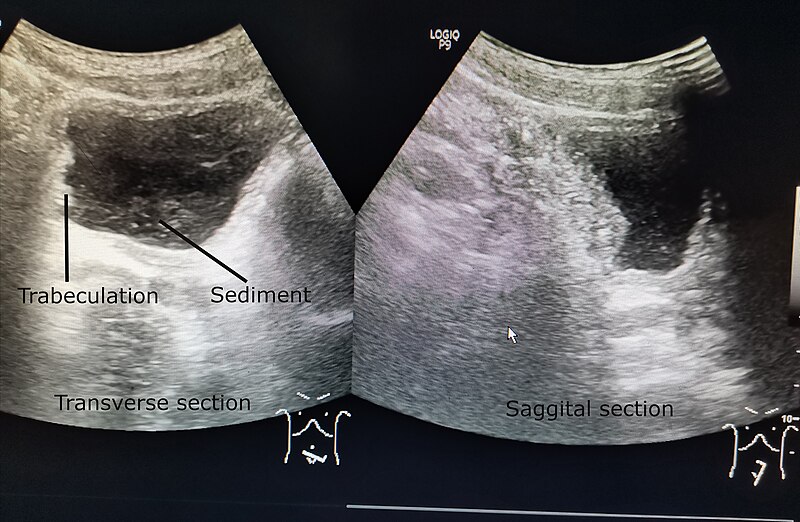

3. Imaging Studies

Several imaging techniques can be used to visualize the bladder and assess wall thickness:

- Ultrasound: A non-invasive method that uses sound waves to create images of the bladder

- CT Scan: Provides detailed cross-sectional images of the bladder and surrounding structures

- MRI: Offers high-resolution images and can help differentiate between benign and malignant growths

4. Ultrasound diagnostics

Allows you to evaluate the internal architecture of the kidneys, prostate, bladder and urethra. Ultrasound may suggest a urinary tract infection, but additional diagnostic tests are needed to confirm.